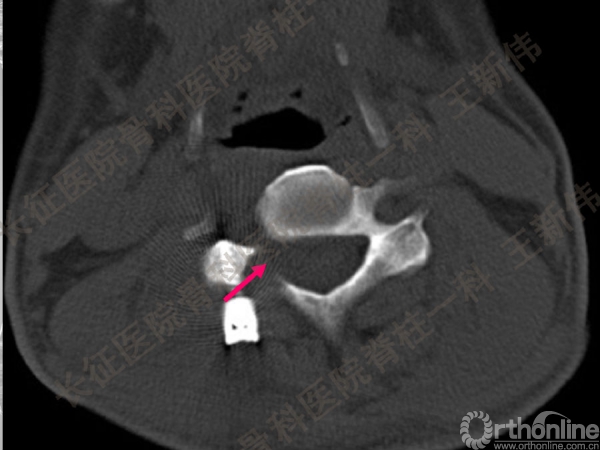

王新伟:颈椎后路通道下手术病例报告及文献回顾

颈椎后路通道下手术有哪些?颈椎后路通道下手术能做哪些事?颈椎后路通道下手术有哪些优势?长征医院骨科医院脊柱一科王新伟副教授通过临床病例报告及文献回顾,给出了他的答案——